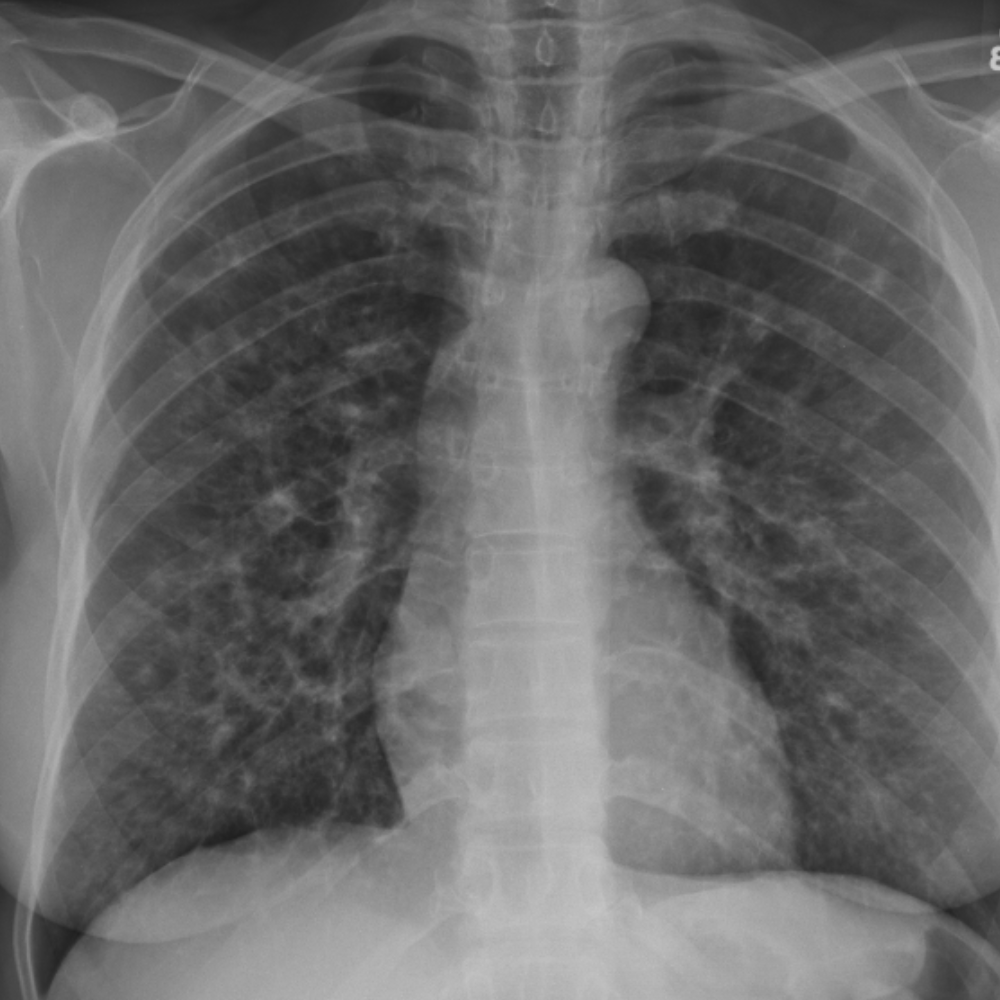

CaseStacks.com - Chest CT Case #16

CaseStacks.com - Chest CT Case #16 www.casestacks.com

case casestacks